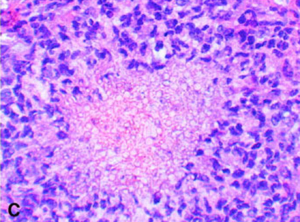

This is a series of HE and PAS stained slides demonstrating intra-sinus inflammation and fungal structures with Aspergillus fumigatus in the rabbit.

Images: Comparative Efficacies, Toxicities, and Tissue Concentrations of Amphotericin B Lipid Formulations in a Murine Pulmonary Aspergillosis Model